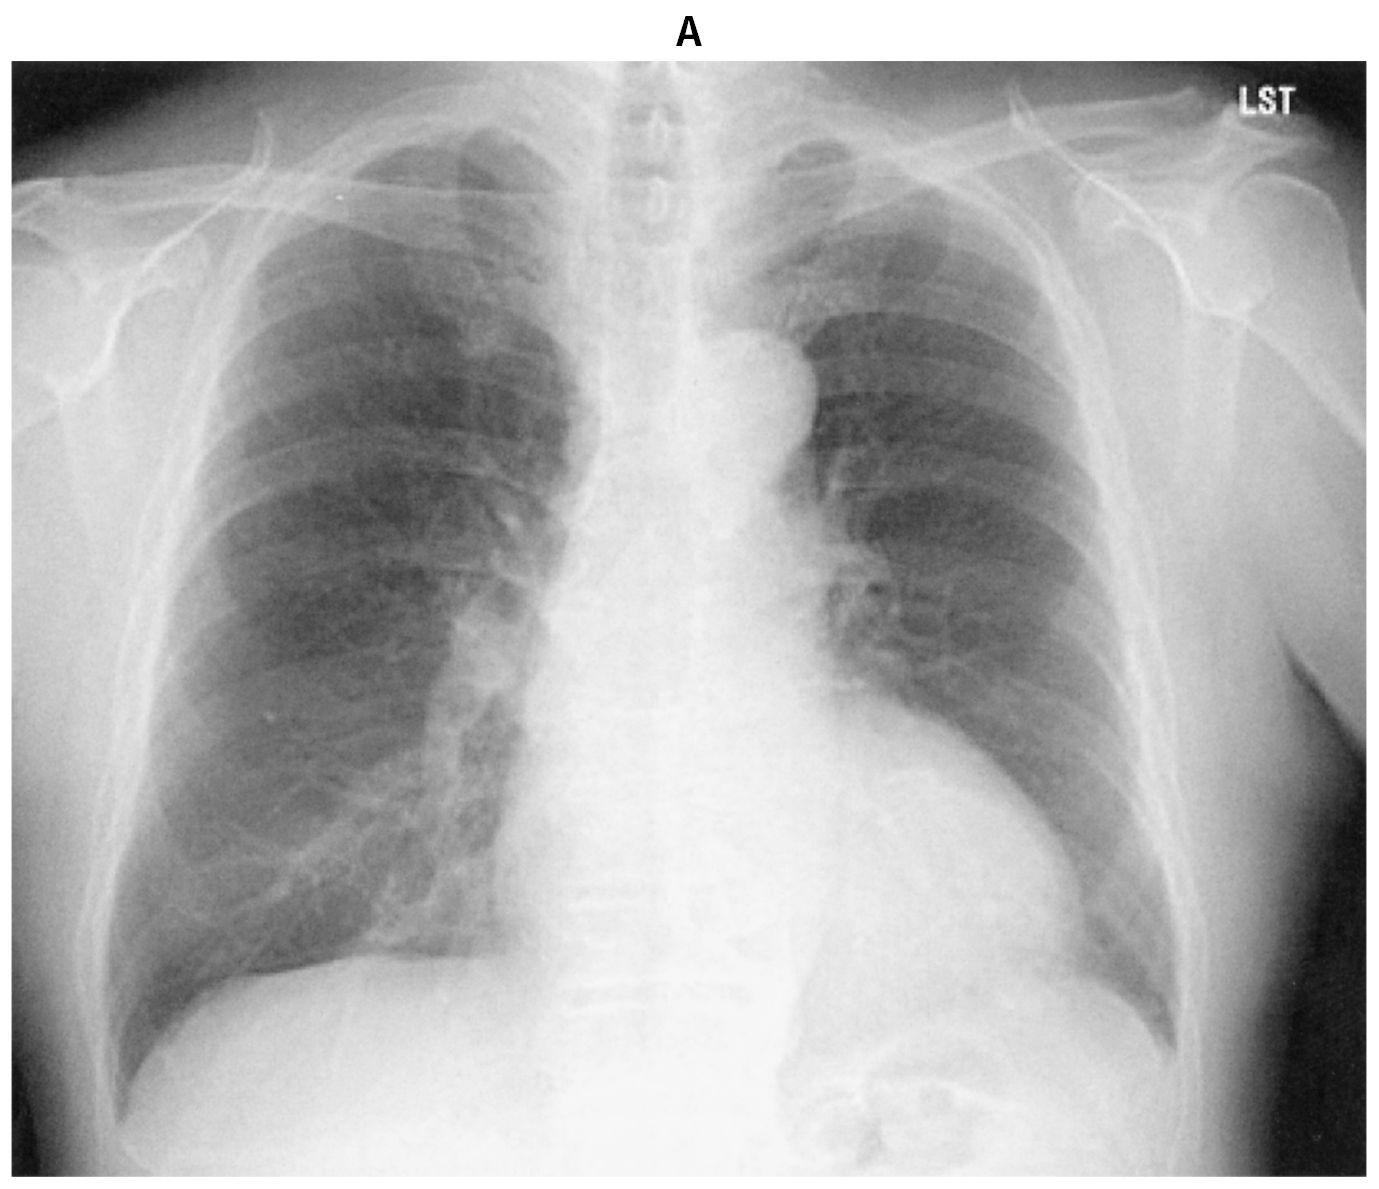

76歳の男性。定期受診で来院した。3年前に拡張期心雑音を指摘され,定期的に心エコー検査で経過観察をしてきた。今回,6か月ぶりの心エコー検査と定期外来で受診し,労作時の息切れを認めた。意識は清明。身長168cm,体重72kg。体温35.8℃。脈拍72/分,整。血圧142/46mmHg。SpO2 98%(room air)。頸静脈の怒張を認めず,呼吸音に異常を認めない。胸骨左縁第3~4肋間にLevine 2/6の拡張期雑音を認める。腹部は平坦,軟で,肝・脾を触知しない。四肢に浮腫を認めない。血液生化学所見:尿素窒素14mg/dL,クレアチニン0.8mg/dL,血糖106mg/dL,HbA1c 6.4%(基準4.9~6.0),BNP 245pg/mL(基準18.4以下)。胸部エックス線写真(A)を示す。心電図では,V4~V6胸部誘導で高電位を認める。心エコー図(B)とカラードプラ心エコー図(C)とを下に示す。心エコー検査では,左室拡張期径69mm,左室駆出率46%,大動脈弁輪の拡大と重症の大動脈弁閉鎖不全症を認める。胸部造影CTでも,著明な大動脈弁基部の拡張を認める。冠動脈造影検査で冠動脈に病変を認めなかった。